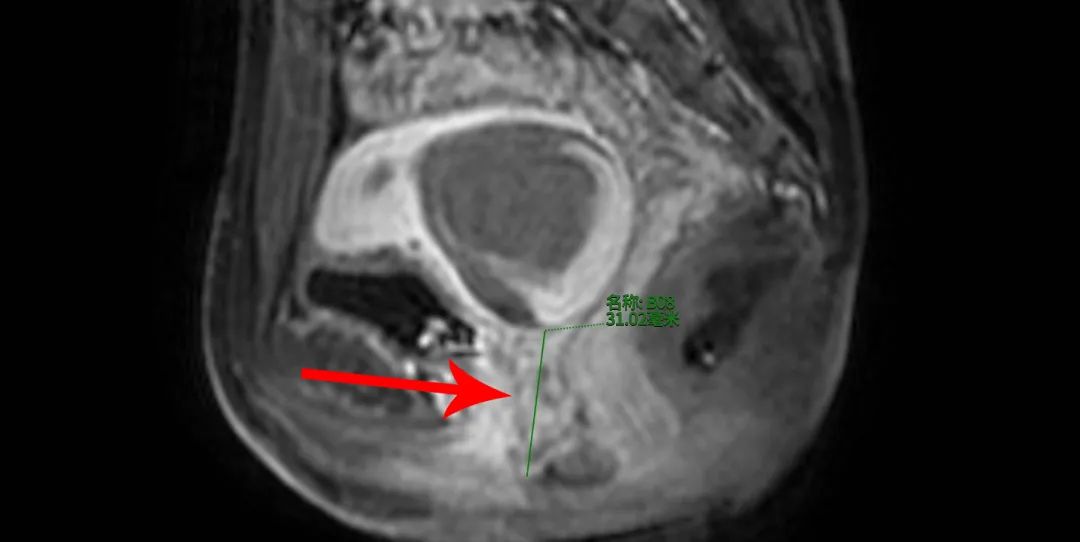

看到您2016年就检查发现子宫腺肌症了,您现在的主要症状是什么?痛经还是月经量多?从23年开始,月经量开始变多,还会有血块,体检查出有轻度贫血。我看您现在子宫体...[详情]